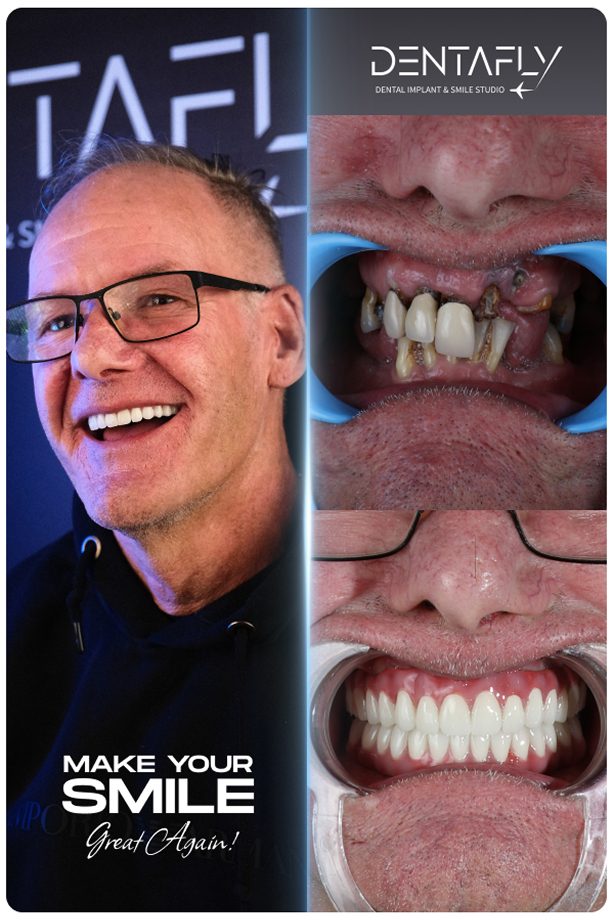

Witness the Transformation: All on 6 Before & After

A permanent full-arch restoration is a masterclass in surgical precision and prosthetic design. Explore our gallery to see how the All on 6 protocol translates into real-world transformations for UK patients—natural finish, restored facial volume, and harmonious smiles.